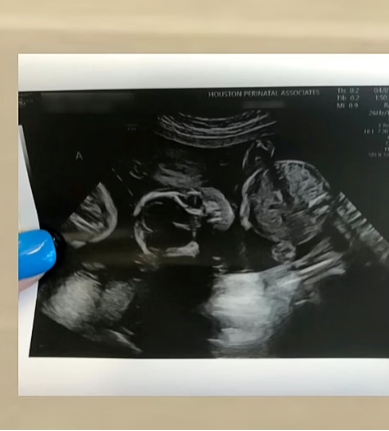

Három gyerekük volt, szerettek volna még egy babát. Elhűltek, amikor meglátták az ultrahang felvételt

Gabinak és Patriknak sem ez az első házassága, a családjuk igazi mozaikcsalád. Mindegyiküknek van egy gyermeke az előző kapcsolataikból, és tavaly még csak egy közös gyermekük volt, Dániel (2). Szerettek volna egy negyedik, és „utolsó” gyereket....